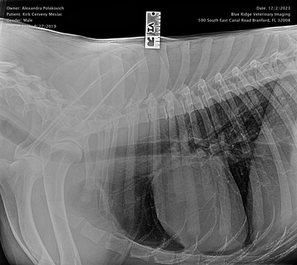

Health Tests: OFA hips good, elbows normal, spine normal (2023)